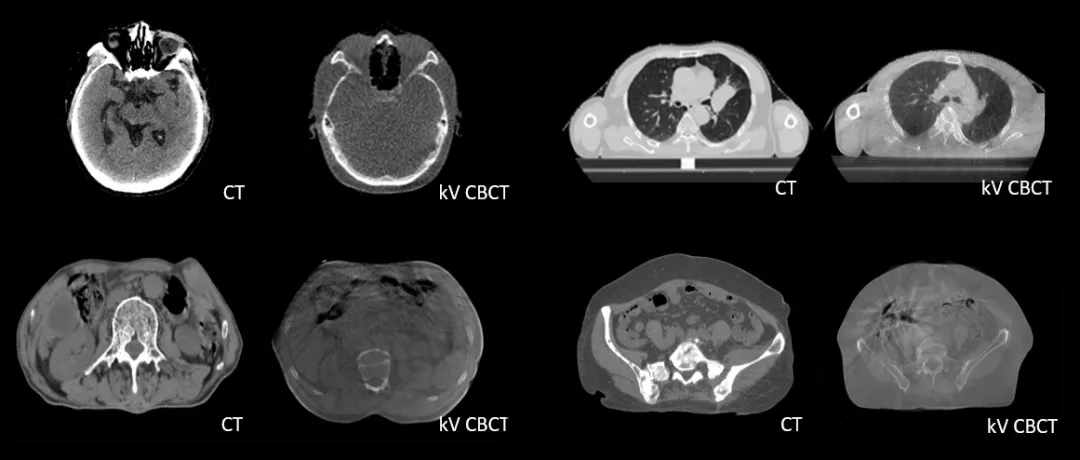

診斷級 CT對比kV-CBCT影像,更好地顯示器官和軟組織的邊界和細節